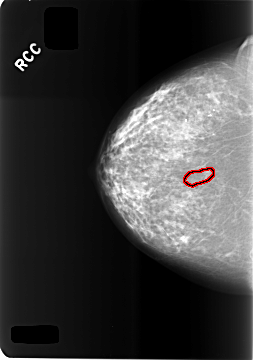

C_0473_1.RIGHT_CC

RIGHT_CC LINES 5760 PIXELS_PER_LINE 4040 BITS_PER_PIXEL 12 RESOLUTION 50 OVERLAY

FILE: C_0473_1.RIGHT_CC.OVERLAY

TOTAL_ABNORMALITIES 1

ABNORMALITY 1

LESION_TYPE CALCIFICATION TYPE FINE_LINEAR_BRANCHING DISTRIBUTION LINEAR

ASSESSMENT 4

SUBTLETY 2

PATHOLOGY BENIGN

TOTAL_OUTLINES 1

BOUNDARY